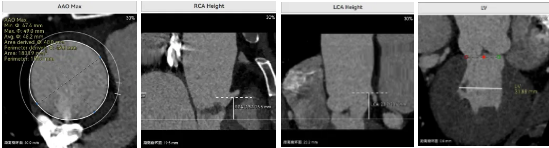

病例概览

患者病史 男性,74y, 因 “发现心脏瓣膜病 1 年,加重伴喘气半年” 入院。门诊检查显示主动脉瓣重度AS并伴轻-中度AR。患者基础疾病较多:胸腹主动脉多发穿透性溃疡、心功能III级等,手术指征明确,但风险极高。 术前CT LVOT- Annulus 倒梯形,对植入瓣膜有挤压位移风险,Annulus直径23.7mm,瓣叶增厚,钙化集中在无冠窦边缘。 左冠脉开口高度可,瓣叶不长、窦部空间较大,无冠脉风险;室间隔膜部较短,有一定PPI风险,心脏角度37.9°;心室较小,有一定循环崩溃风险,术前注意补液。 术前造影角度及入路:血管入路散在钙化、无迂曲;主动脉弓条件好、双侧股动脉直径大、右股穿刺点侧壁存在环形钙化 左右重合位:RAO 7° CAU 21° 右窦中心位:LAO2 1° CAU 1° 手术策略 20mm球囊预扩后植入AV26瓣膜,同时做好预防循环崩溃、传导阻滞的应急预案。 术中挑战 1)球囊预扩:20mm球囊预扩时无明显 “腰征”,但存在少量反流,提示瓣膜钙化与解剖结构对扩张的阻力不均 2)首次释放偏差:第一次定位释放时,瓣膜在 “开花” 过程中下滑约 3mm,工作位观察显示小弯侧瓣周漏较多(深度超过完全覆膜区),需二次调整。 3)二次精准定位:以猪尾导管为参照,将定位点调整至 “猪尾 - 2mm” 处,结合真实窦底深度(较深)重新释放,最终瓣膜位置稳定,瓣周漏显著减少。 术后即刻效果: 瓣膜形态良好,跨瓣压差从术前的 67mmHg 降至 6mmHg,且无明显瓣周漏,冠脉开口通畅; Commisural Alignment 术后即刻超声: Prostyle A®预装干瓣——助力临床最优化解决方案: √ 平衡的径向支撑力:特殊的解剖结构下位置形态良好,术后跨瓣压差大幅降低,血流动力学改善明显; √ 80%可回收设计:支持术中二次调整释放位置,保证精准释放; √ 平衡的收腰设计&Commissural Alignment设计: 为患者后期冠脉PCI保留了生命通道;